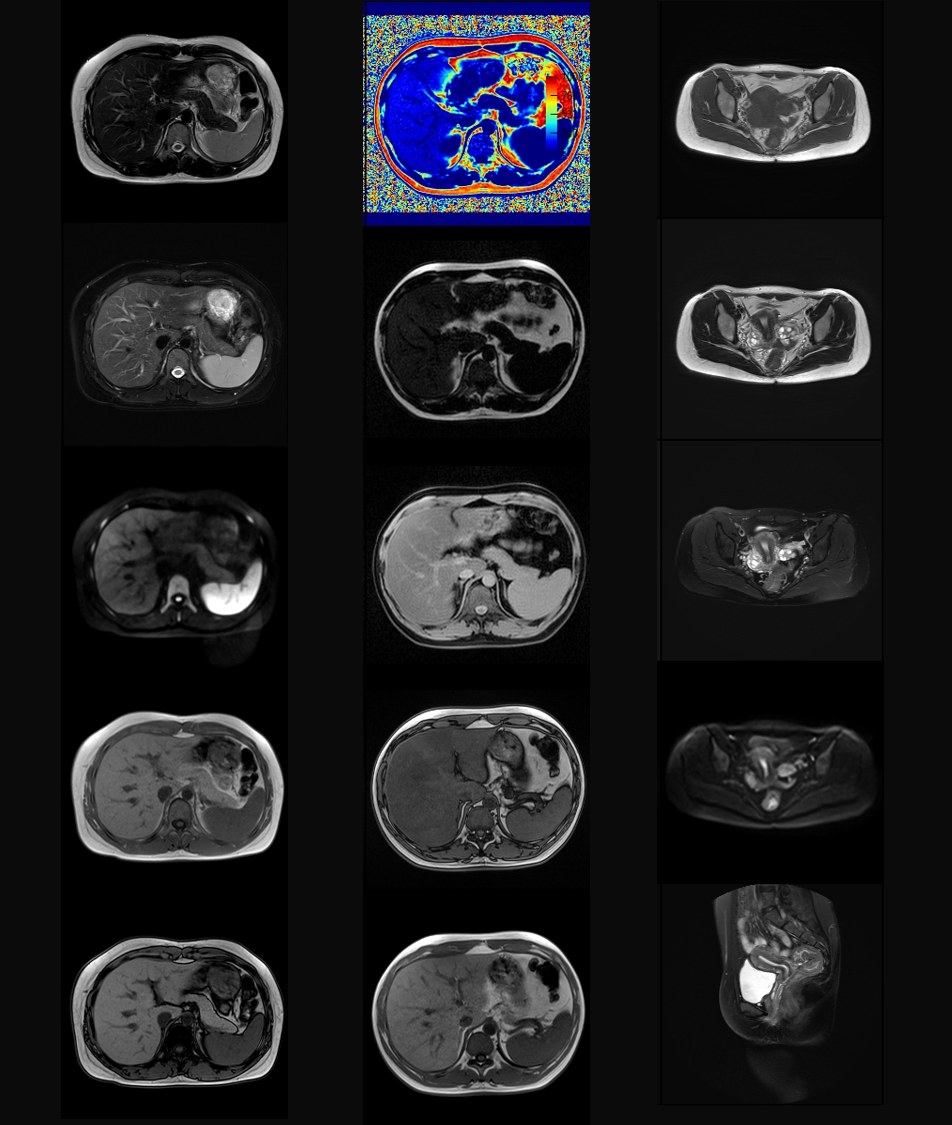

先導科技集團官網

腹部&盆腔